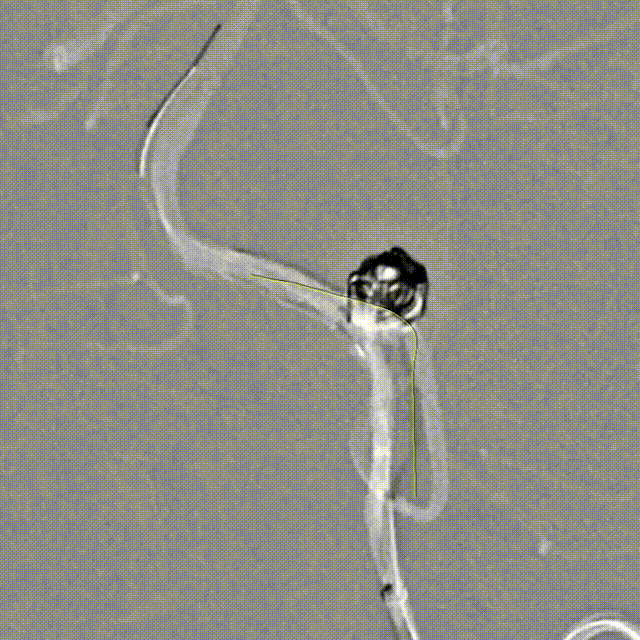

Tubridge Plus Case 2